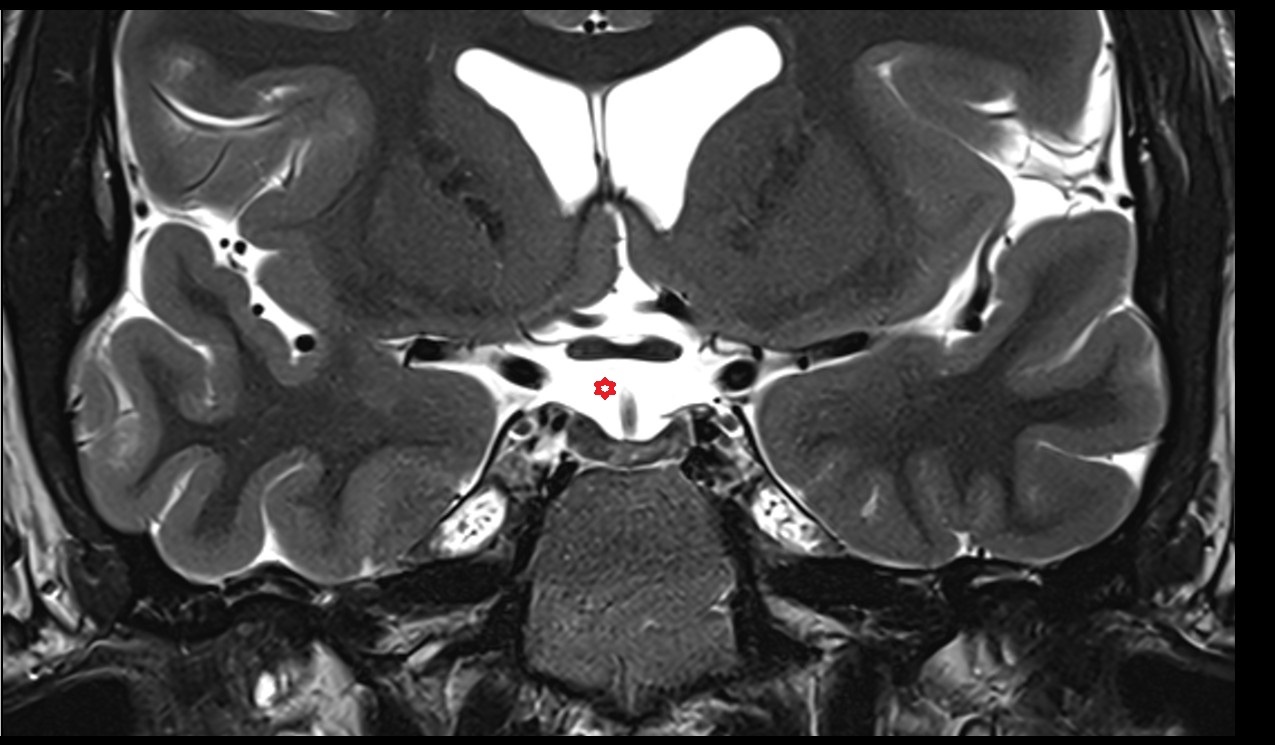

- Fourth ventricle

- Cerebral aqueduct